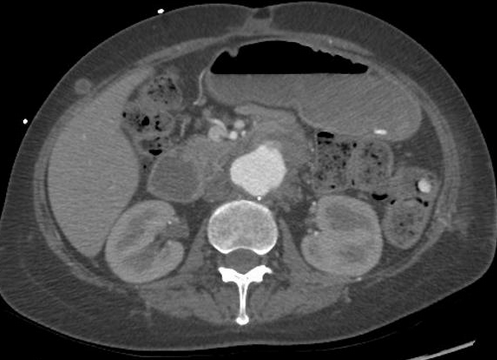

Repeat abdominal CT scan demonstrating complete resorption and disappearance of air from the stomach and the portal venous system (Courtesy Dr. V. Penopoulos)